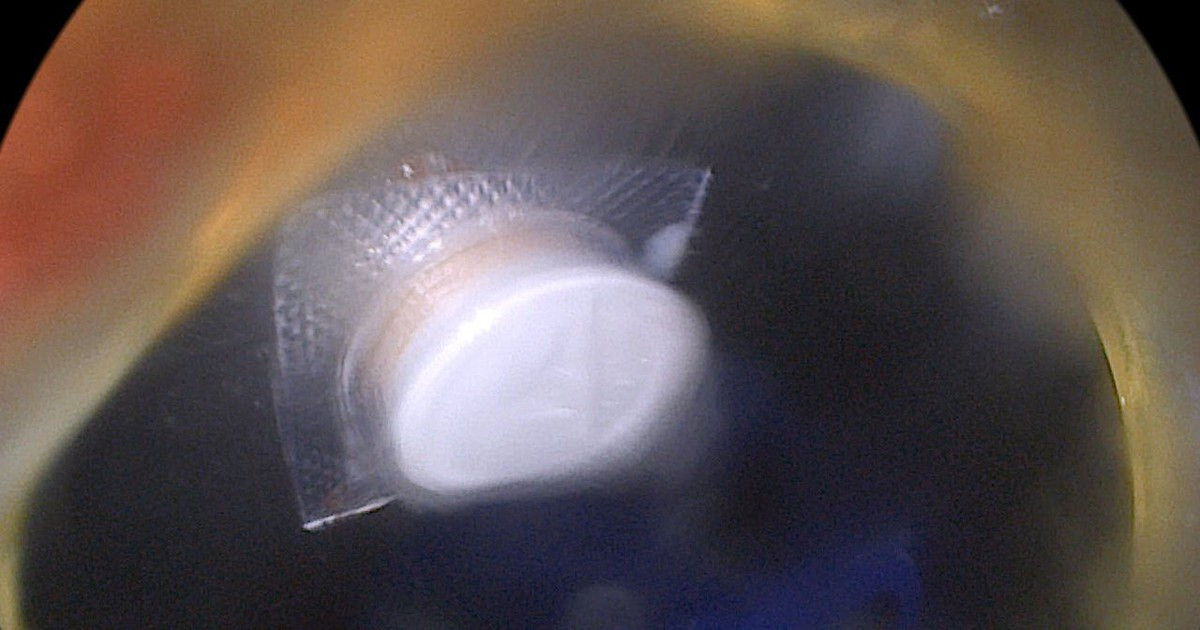

Một bệnh nhân mắc hội chứng Cushing. (Ảnh minh họa: Bệnh viện cung cấp)

Qua thăm khám, ghi nhận người bệnh có khuôn mặt tròn, đỏ, mỡ dồn vùng cổ, da mỏng và dễ bầm. Qua đó, bác sĩ đánh giá, người bệnh có dấu hiệu gợi ý hội chứng Cushing (Cushing syndrome) kèm suy tuyến thượng thận mạn, liên quan đến việc sử dụng corticoid (corticosteroids) kéo dài.

Theo bác sĩ, những người lạm dụng corticoid kéo dài có thể xuất hiện nhiều thay đổi về ngoại hình và sức khỏe. Về hình thể, người bệnh có thể có khuôn mặt tròn đỏ, tích mỡ vùng cổ, tăng mỡ vùng bụng nhưng tay chân lại teo nhỏ do giảm khối cơ. Trên da có thể thấy da mỏng, dễ bầm tím hoặc xuất hiện các vết rạn màu đỏ tím.